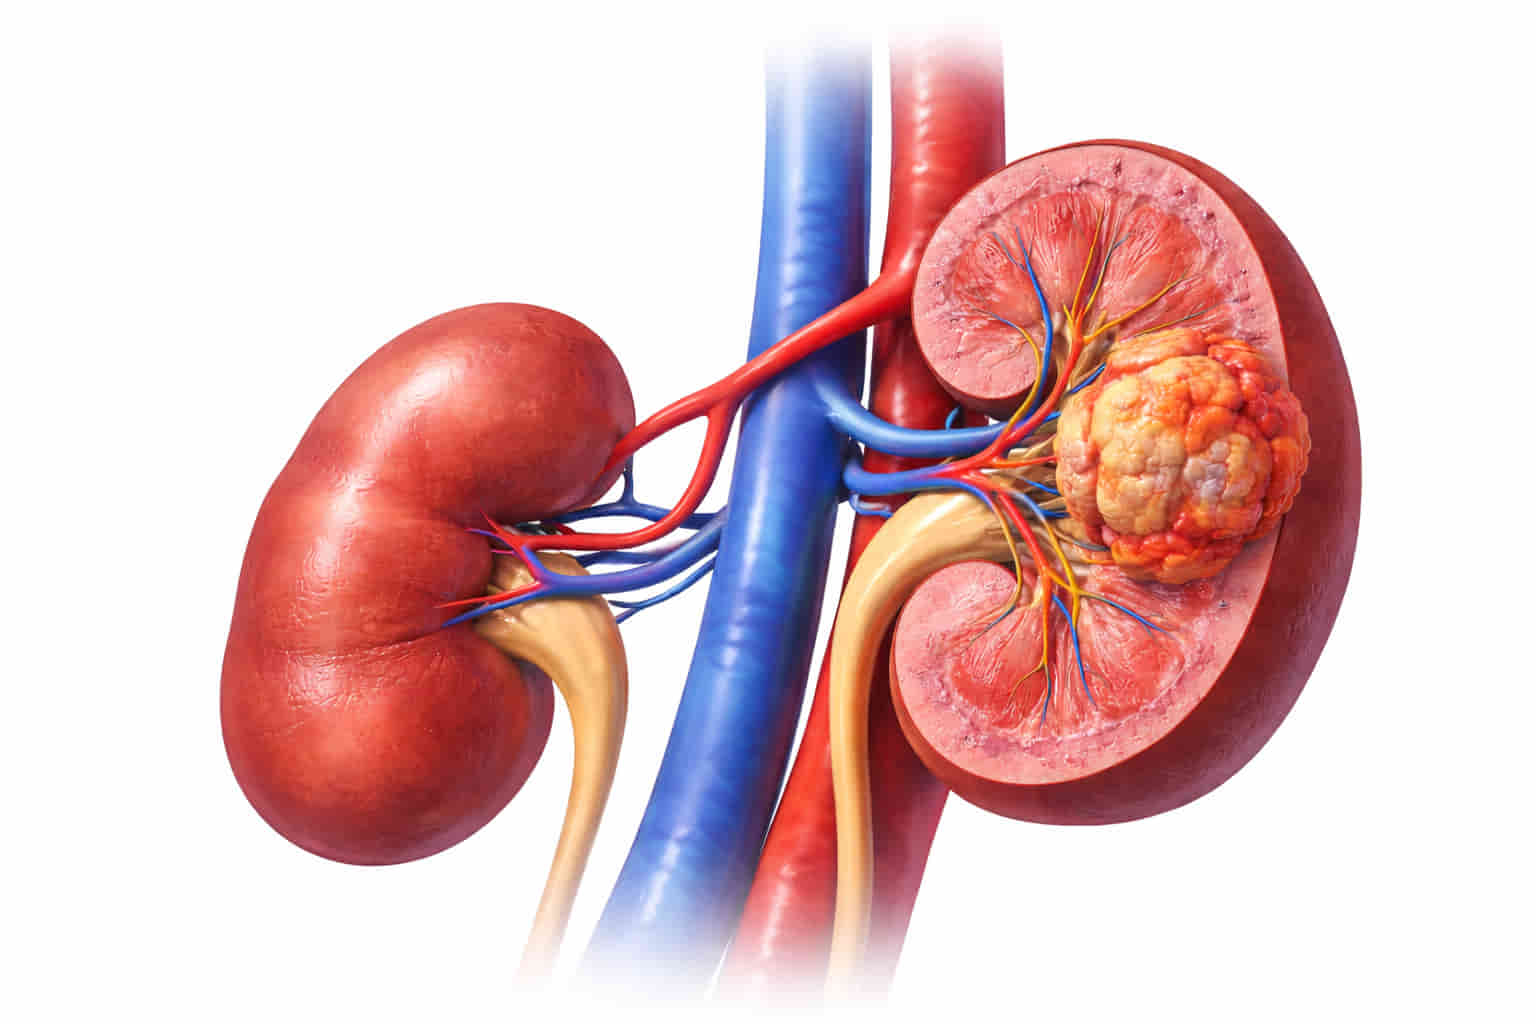

Renal Cryoablation is particularly effective for:

- Small Renal Masses: Tumors that are typically 4cm or smaller (Stage T1a).

- High-Risk Patients: Individuals who may not tolerate general anesthesia or major surgery due to age or other health conditions (e.g., heart or lung disease).

- Single Kidney Patients: Those who have only one functioning kidney and need to preserve as much healthy tissue as possible.

- Patients seeking a minimally invasive option with faster recovery and less pain

Renal Cryoablation is particularly effective for:

- Small Renal Masses: Tumors that are typically 4cm or smaller (Stage T1a).

- High-Risk Patients: Individuals who may not tolerate general anesthesia or major surgery due to age or other health conditions (e.g., heart or lung disease).

- Single Kidney Patients: Those who have only one functioning kidney and need to preserve as much healthy tissue as possible.